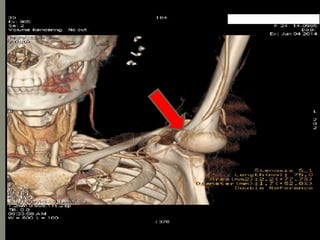

 CT angiogram:

it is non invasive and detects early

 First totreat as medically as shown by ESR & symptoms pt was in active stage and then to do intervention of left subclavian artery  So Pt was prescribed deltaacortil 30 mg per along with Methotrexate 10 mg weakly  Pts symptoms improved ESR dec: 70  08  Methotrexate was stopped due to hepatotoxicity  And finally stenting of left subclavian artery was done